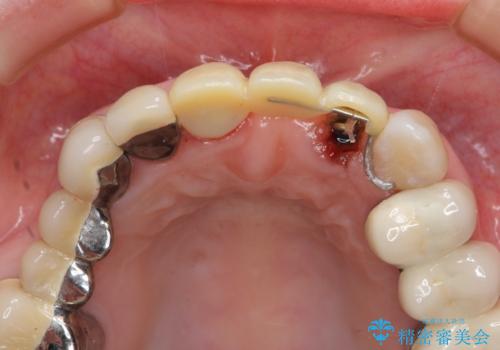

歯肉縁下カリエスも認められるため、挺出を行いセラミックブリッジを審美的に新製します。

虫歯が深くなった場合、挺出や歯周外科を行い歯周組織の状態を改善することでより安定した状態で予知性の高いセラミックブリッジを製作することが可能となります。